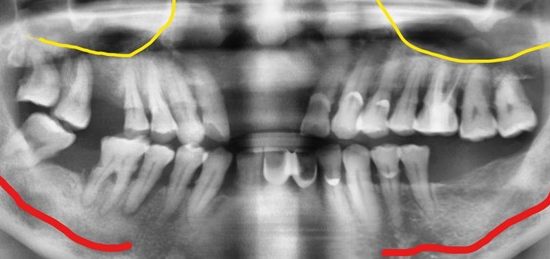

Răng hàm trên

Răng hàm dưới